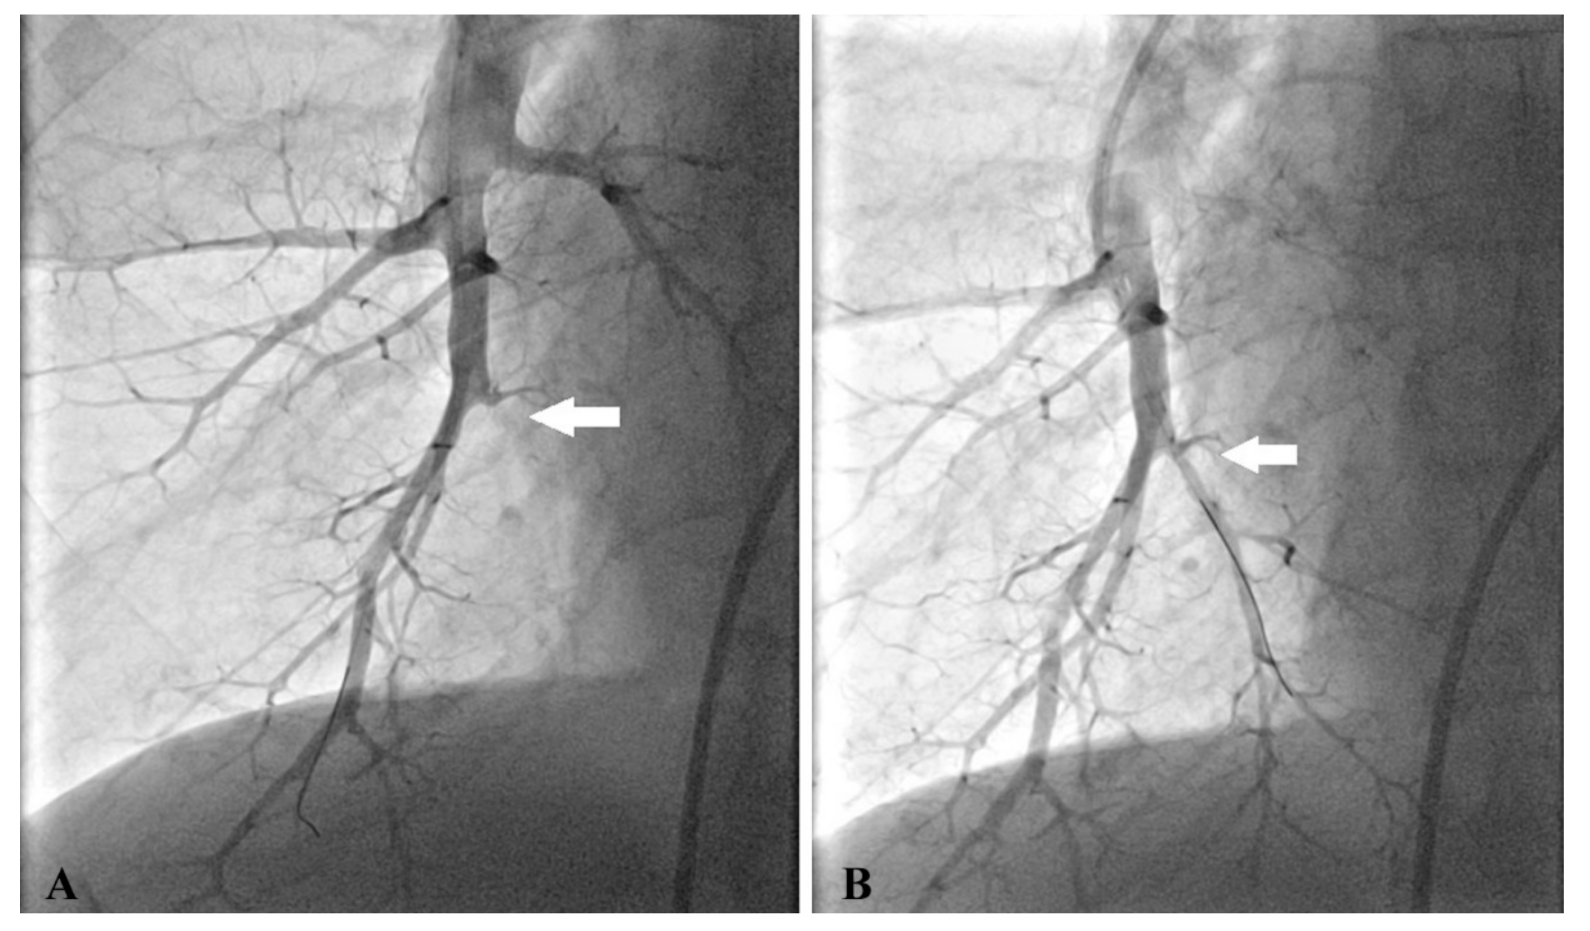

We used predominantly femoral access, but a jugular site was employed for a few interventions as well. At the beginning of each procedure, right heart catheterization was performed using a 7 French sheath and Swan–Ganz thermodilution catheter (B Braun Melsungen AG, Germany) to measure hemodynamic parameters. Then, BPA was initiated by the replacement of the 7 French sheath with a guiding sheath (6 French Destination 65 cm or 6 French Balt 80 cm). A 6 French guiding catheter (Multipurpose, Judkins right 4 or 5, Amplatz left; Boston Scientific, Marlborough, MA, USA) was introduced and unfractionated heparin at a dose of 2500 IU was administered into the guiding catheter. The guide wire (PT2 Moderate Support, Boston Scientific, Marlborough, MA, USA or Asahi Sion Blue, Asahi Intecc Co, Japan) was placed into the target branch. We selected undersized balloons (1.5–4/20 mm, Abbott, Abbott Park, IL, USA) to avoid pulmonary vascular injury. The larger balloons were used in later sessions for postdilatation. The lesions were dilated by multiple balloon inflations at 2–8 segmental or subsegmental branches during one session. We had never exceeded the limit of 300 mL contrast medium and 40 min of total time of skiascopy in any session. A subsequent procedure was planned within 1–2 months. Figure 1 demonstrates selective pulmonary angiograms and BPA result in an inoperable patient with CTEPH.

Figure 1. Selective pulmonary angiogram of the right lower lobe shows total occlusion of segmental branch A10 (A) and its opening after the first BPA procedure (B).